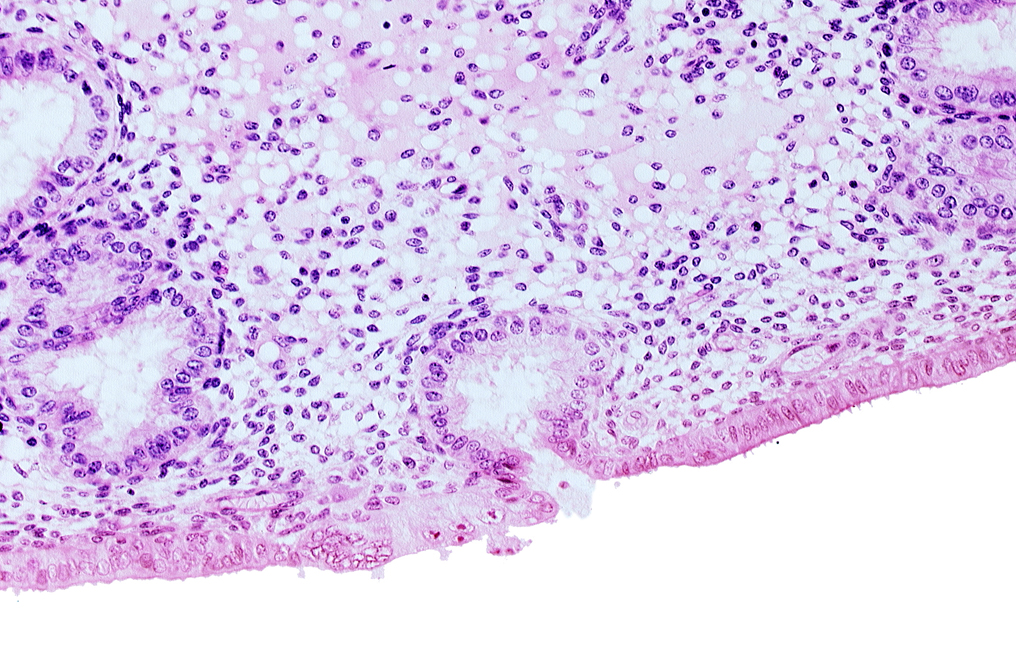

Carnegie Embryo #8020 | Location: 06-05-09

Keywords: disrupted endometrial epithelium, edematous endometrial stroma (decidua), endometrial epithelium, lumen of endometrial gland